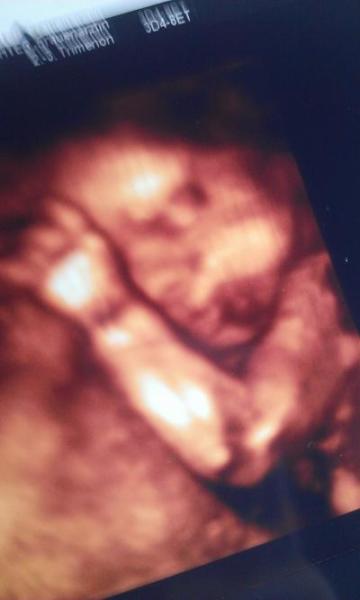

Ich hab ja immer fleißig eingeölt den Bauch, aber jetzt hat mir der Nikolaus tatsächlich links und rechts unten SS-Streifen mitgebracht.. der Sack! :D Man könnte sagen "I earned my stripes", aber irgendwie bin ich jetzt suuuper unzufrieden mit meiner Murmel. Mein kleiner Mann bewegt sich in letzter Zeit auch unheimlich viel und seeeehr langsam, sodass mir manchmal echt anders wird davon. Habe das Gefühl er liegt mit dem Kopf noch im Becken, krümmt sich nach links und haut seine Füße immer rechts in meine Seite. Das ist besonders in den Vorlesungen, wenn ich still sitzen muss, sehr unangenehm und wenn ich anfange leise herumzustöhnen, müssen meine Kommulitonen immer schon vor sich her grinsen Auch muss ich dadurch zwangsweise gerade sitzen, denn kaum sitze ich ein bisschen krumm, hab ich das Gefühl, dass seine Füße zwischen meinen Rippen hängen. Achja, dann habe ich noch vor zwei Wochen bei meiner Tante (sie ist FA) einen 3D Ultraschall gemacht und mir den Kleinen genau angeguckt. Sieht schon aus wie ein hübsches Baby, aber noch sooooo dünn! Er hat ja auch noch Zeit. 3D war aber richtig cool und super interessant! Viele Grüße! (ab morgen 30. SSW juhuuu!)

Bild zu Wehwehchen und 3D Bild - Forum für Februar - Mamis